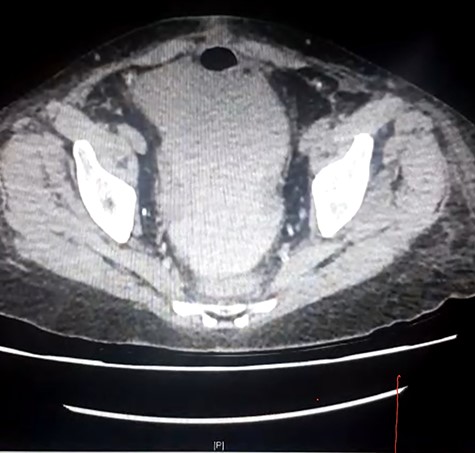

She presented to her local hospital due to sudden onset of severe abdominal pain with associated nausea, vomiting and diarrhoea. She was tachycardic though normotensive on presentation and found to have generalized severe abdominal pain. CT imaging revealed an SBO with an evidence of ischaemia as well as an obstructed ureter and renal collecting system within the allograft (Fig. 1). She underwent laparotomy, division of band adhesion in the left pelvis and 1.2 m of small bowel resected due to ischaemic necrosis with an end-to-end hand sewn anastomosis.

Initial CT demonstrating SBO and obstructed renal allograft/ureter (double obstruction).